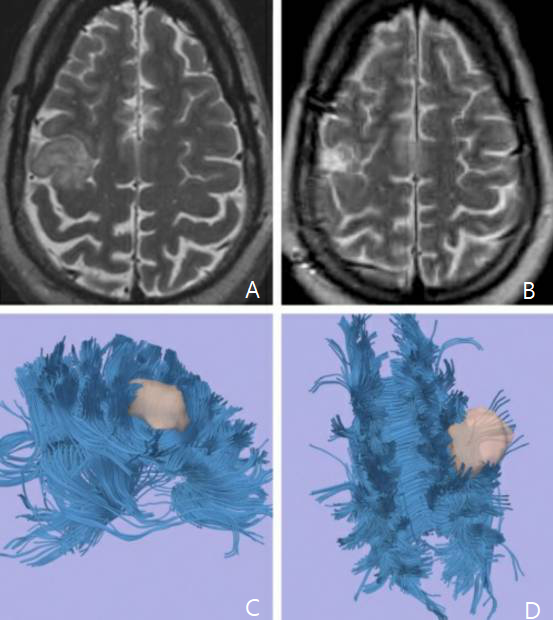

图5. 术前影像学提示为低级别胶质瘤,位于右侧脑室周围并扩展至额叶内侧。冠状位(C)和矢状位(D)fMRI提示肿瘤位于感觉运动功能区。扩散张量成像DTI(E)显示肿瘤推挤运动功能纤维束移位。